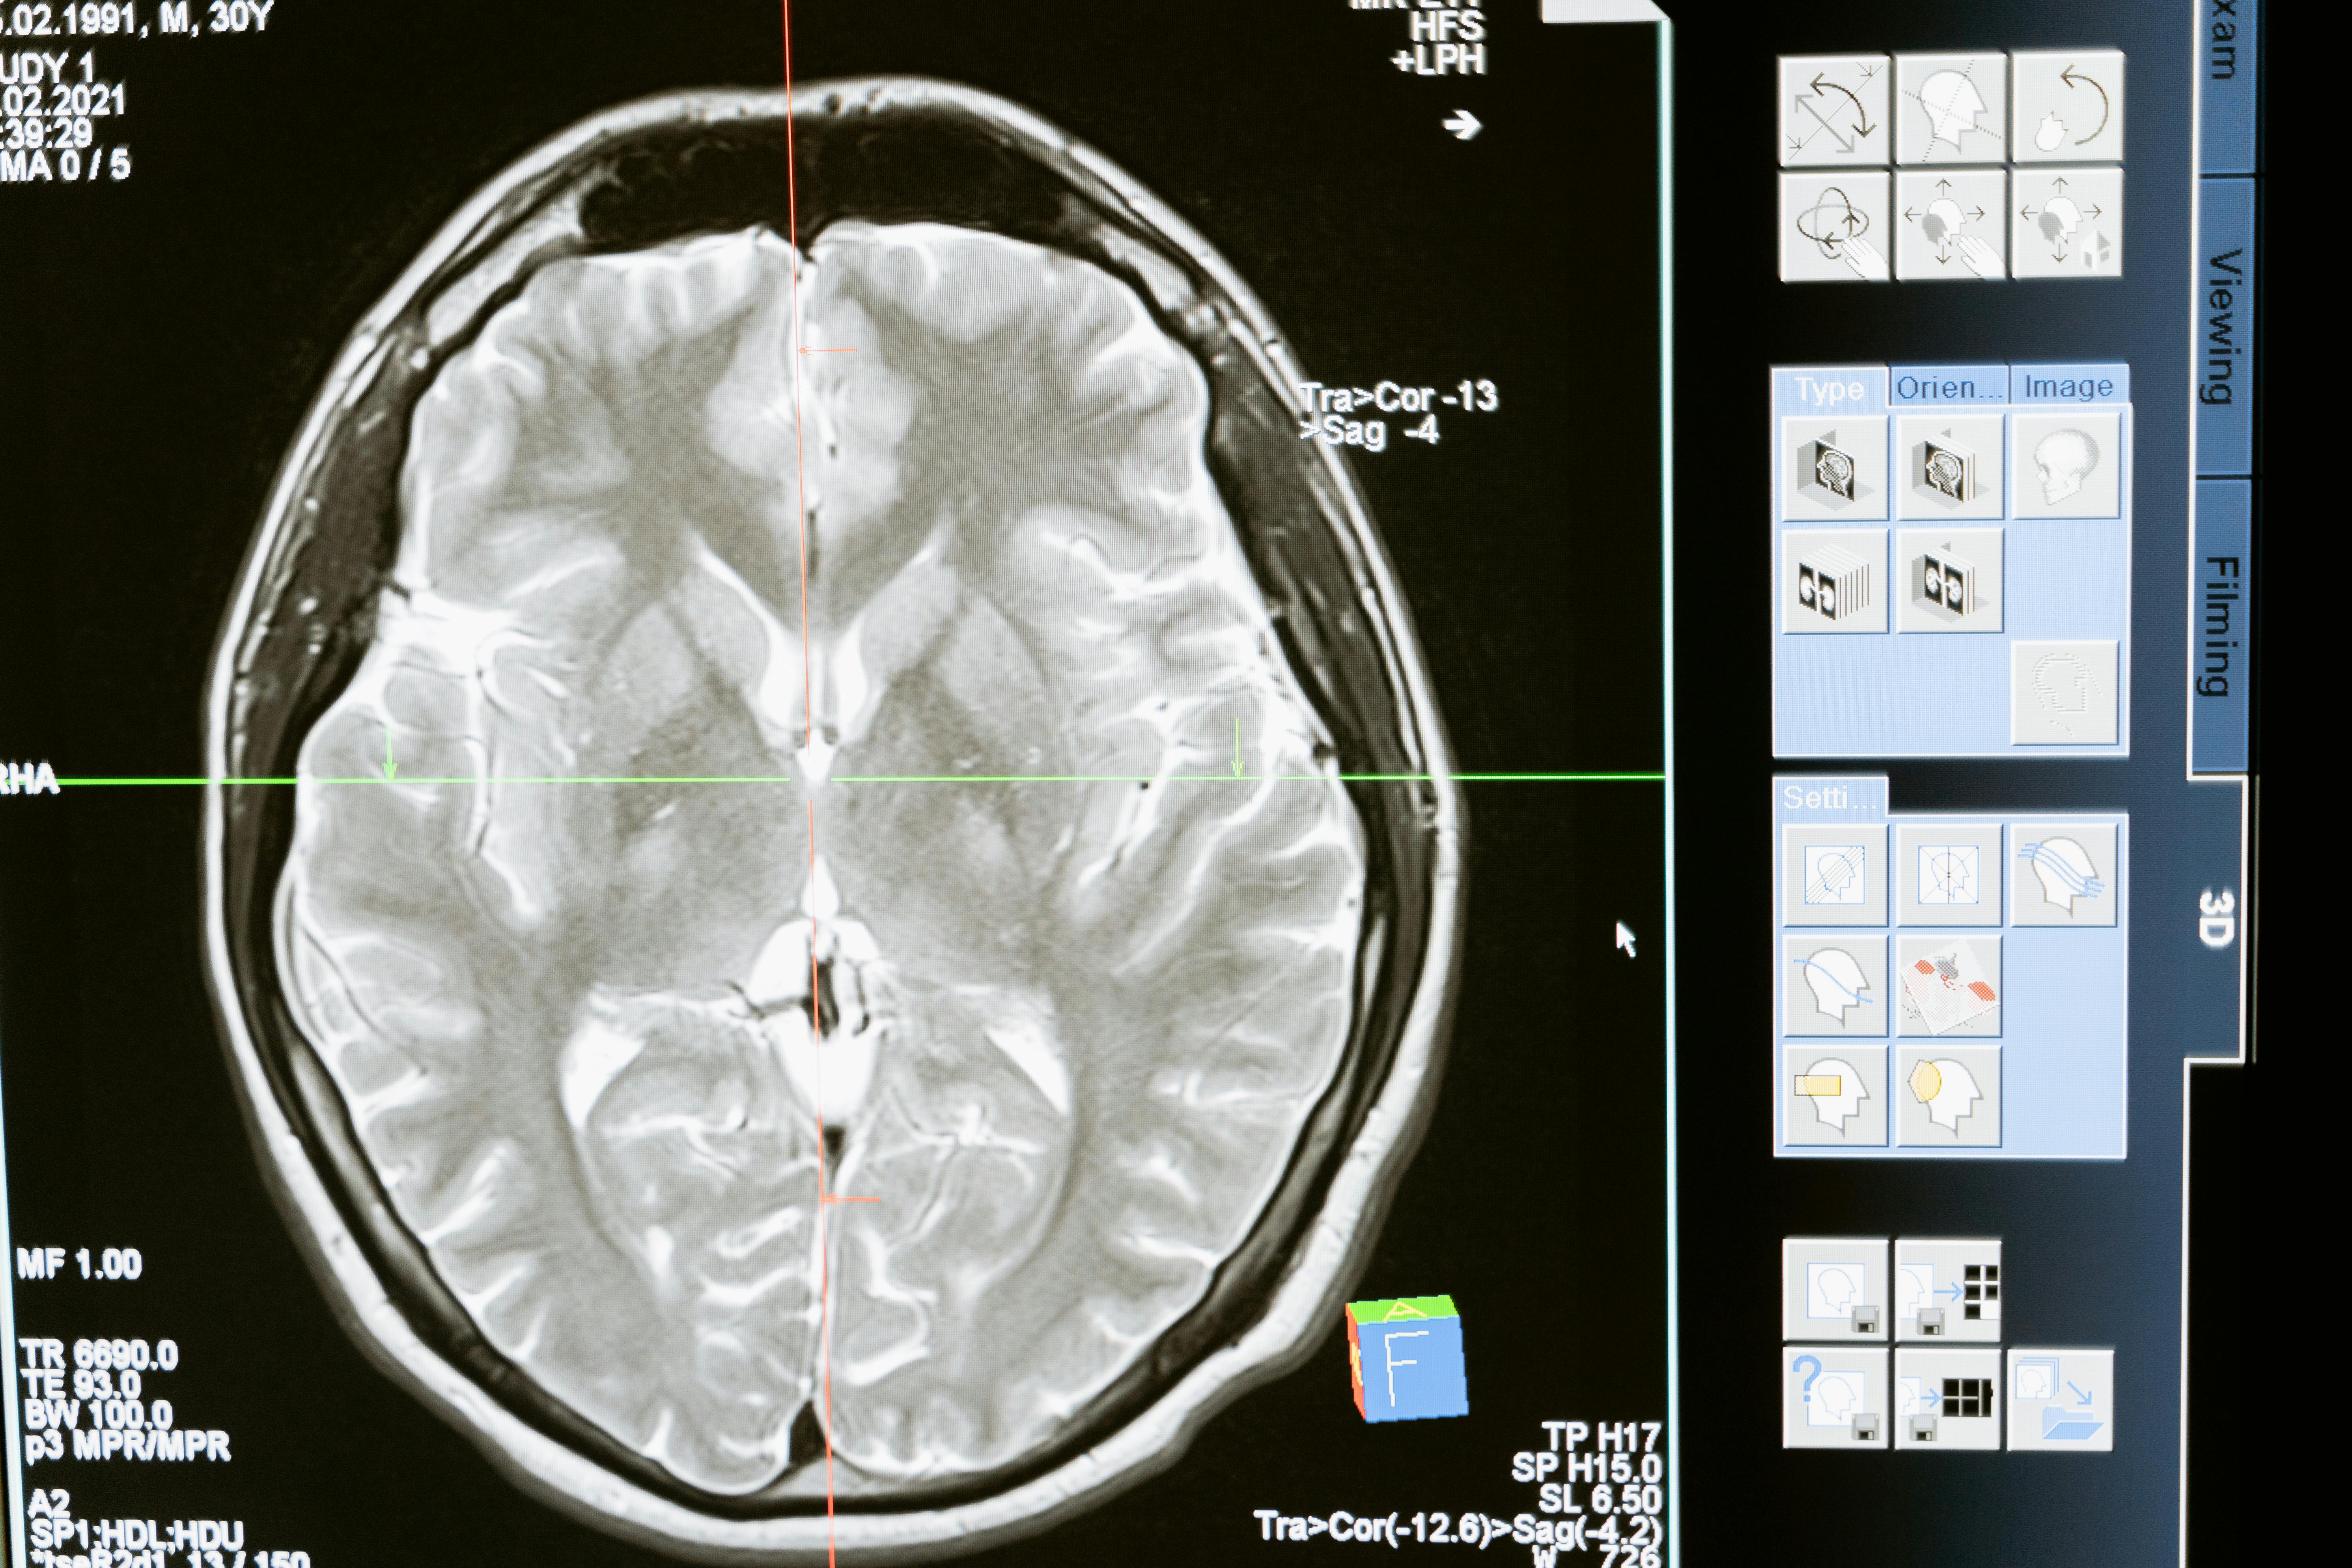

15. Chiari Malformation: Central Nervous System Influence

Chiari Malformation is a structural defect where brain tissue extends into the spinal canal, potentially putting pressure on the brainstem and spinal cord. Why it's unique: This is a central nervous system cause, not a primary vascular problem. The brainstem controls autonomic functions, including temperature regulation and circulation. When this control center is compromised, it can disrupt the nerve signals responsible for vasoconstriction and temperature sensing throughout the body, leading to unexplained, persistent coldness in the extremities. Action: Often discovered incidentally via MRI. Diagnosis is followed by neurological evaluation. While treatment for the malformation varies, understanding this cause shifts focus from peripheral vessels to central nervous system regulation.